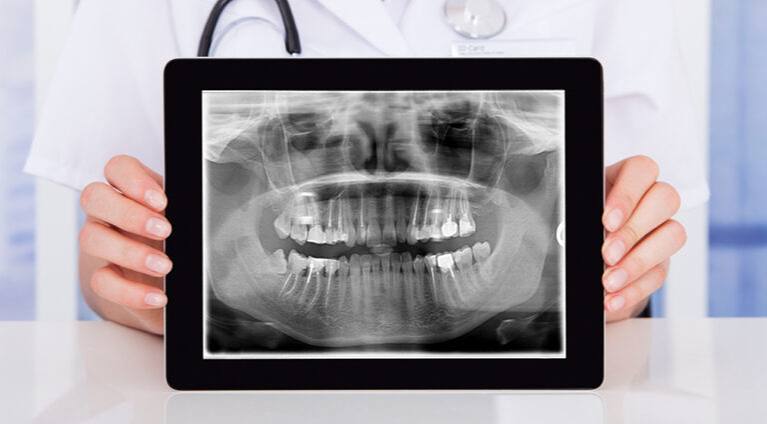

Necessity of a Microscope in Dentistry at DentalClinic24 – How Magnification and Visual Control Improve Treatment Precision

Precision in dentistry is determined not only by the clinician’s experience, but also by the level of visual control over the working field during treatment. Within the clinical approach of